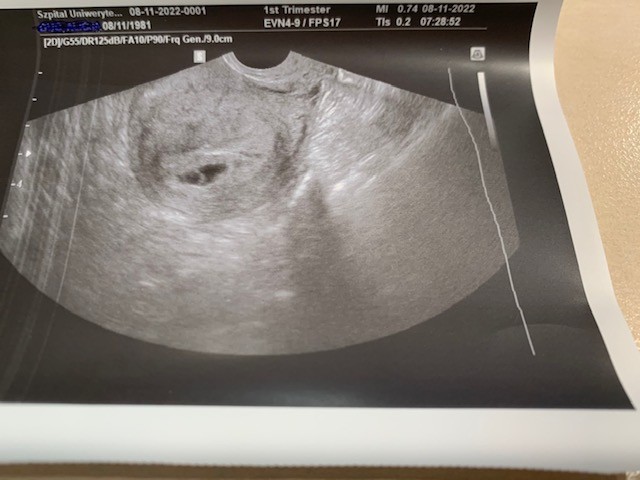

Niestety zarodka i serduszka brak, wszystko wygląda dobrze, tylko wygląda to ma 5-6 tydzień ciąży (widać mały pęcherzyk żółtkowy - nie znam wymiarów, bo nie ma na wydruku)

Załączam też wydruk z usg (niestety mało wyraźne).